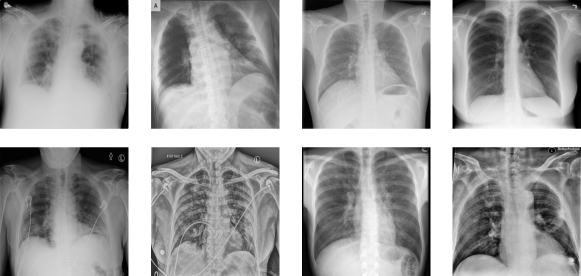

Figure 1: Images from the COVID-19 radiography dataset and COVIDx CXR-3 dataset. The left half are COVID-positive images while the right half are COVID-negative images. Top: COVID-19 radiography dataset, and Bottom: COVIDx CXR-3 dataset.

We evaluate CECT on the COVID-19 radiography dataset and the COVIDx CXR-3 dataset. The COVID-19 radiography dataset is collected by researchers from Qatar University and the University of Dhaka together with their collaborators. There are 3616 COVID-positive and 10192 COVID-negative images in the COVID-19 radiography dataset. The COVIDx CXR-3 dataset is a chest X-ray dataset collected from 16,648 patients at different locations. There are 30386 images in the dataset and the dataset is composed of two parts. The first part is for training and validation with 29986 images, while the second part is for testing and is composed of 400 images. For the first part, 15994 images are labeled as positive while 13992 images are labeled as negative. Regarding the second part, 200 images are labeled as positive and the remaining 200 images are labeled as negative. Illustration images from the two datasets can be found in fig. 1.